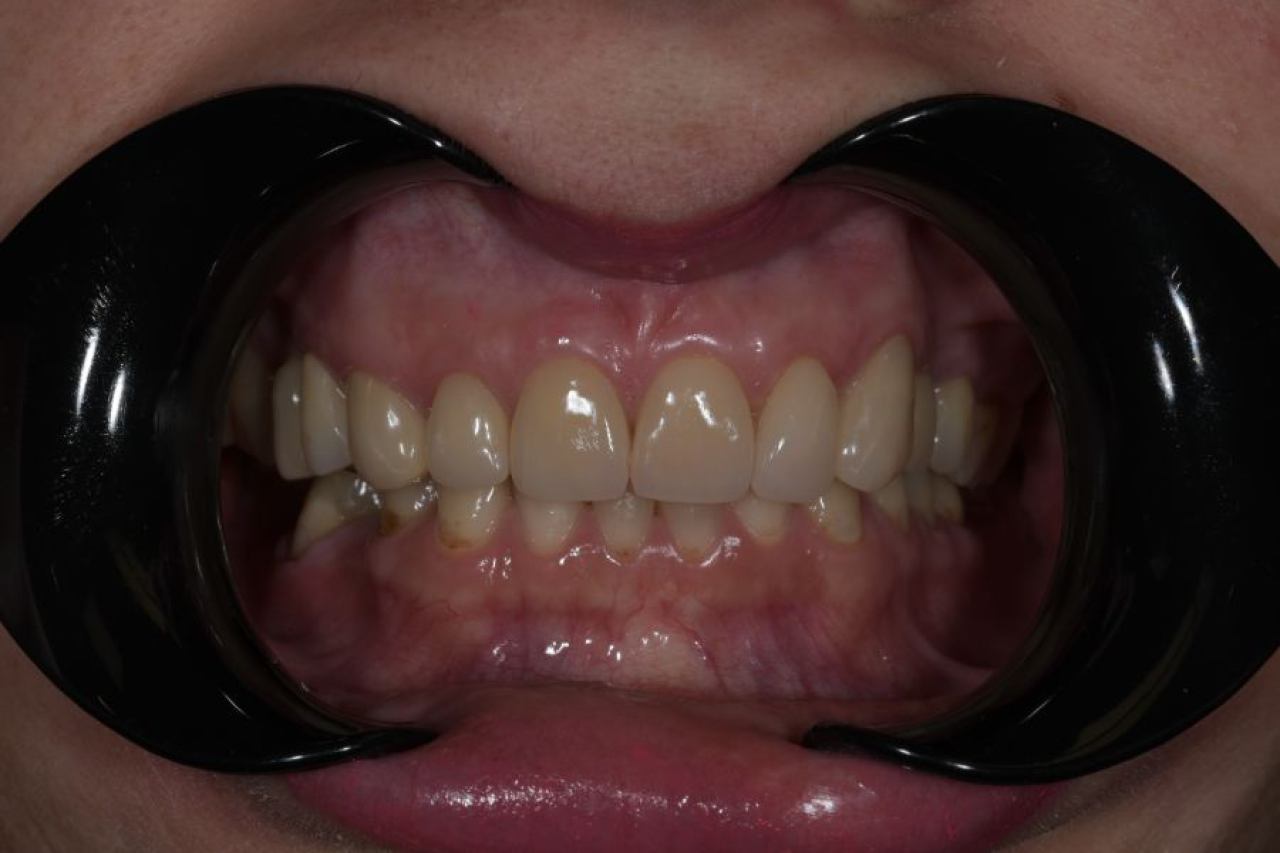

Protetika - mostovi i krunice

Dentalna protetika uključuje fiksne i mobilne radove kojima se nadoknađuje djelomična ili potpuna bezubost. Njihov cilj je povratiti funkciju žvačnog sustava i u konačnici, vrhunsku estetiku.

Marković Dental Clinic u svojoj ponudi ima metalkeramičke radove, potpunokeramičke radove, te u narodu zvane „bezmetalne", odnosno zirkonske radove.